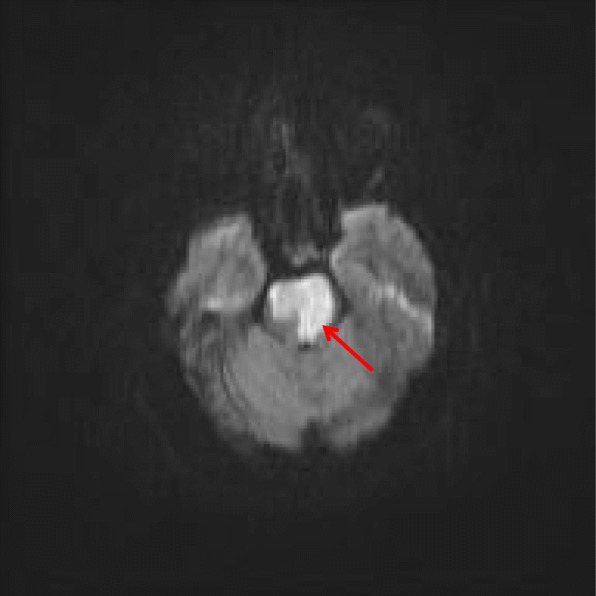

On day 3 of admission, when the patient had been weaned off sedation and paralytic therapy, she demonstrated decorticate posturing, intact gag and cough reflex, positive Babinski reflexes bilaterally, and intact pupillary reflexes. The patient’s motor strength was dramatically decreased in both upper and lower extremities. She was obtunded, unable to follow commands, and opened her eyes spontaneously. On day 4 of admission, she was minimally responsive to commands and was able to communicate only with vertical eye movements. Repeat noncontrast CT showed hyperdensity in the basilar artery, suggestive of occlusion due to thrombosis, which was not present in the initial CT findings (Fig. 1). Findings of lumbar puncture with cerebrospinal fluid examination and electroencephalography (EEG) were unremarkable. MRI showed large foci of abnormally restricted vessels of the brainstem with recent infarction, occurring bilaterally with no observed hemorrhage (Fig. 2). MRA revealed complete loss of flow-related signal within the distal basilar artery (Fig. 3).

Fig. 2.

Magnetic resonance imaging of the patient’s brain without contrast from February 9, 2015. A large focus of abnormal restricted diffusion is demonstrated in the brainstem (red arrow), consistent with recent infarction. This primarily affects the cranial aspect of the pons, possibly extending into the midbrain. This is a bilateral finding, with more extensive involvement on the left. This is concordant with findings from computed tomography of the patient’s head on February 7, 2015. Mild associated mass effect and swelling are present at this time